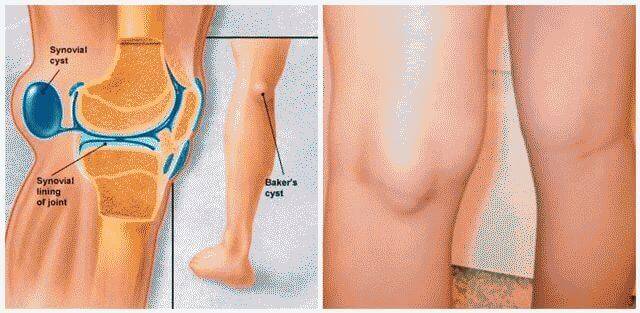

Анатомия коленного сустава: изучение анзерита и его влияния